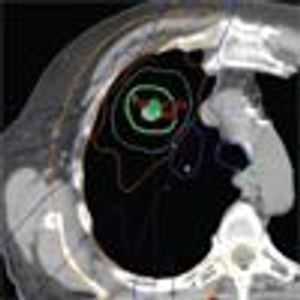

Three randomized trials of SBRT vs surgical resection closed due to poor accrual, but an analysis of patients treated in these trials suggested that SBRT might even be superior to surgery. New trials are underway to further assess the question of whether SBRT can be the definitive treatment for early-stage NSCLC instead of surgery.